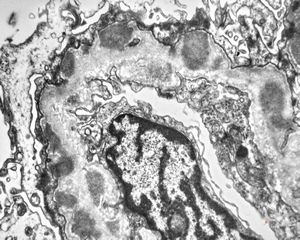

F,14y. | Alport syndrome - split and laminated, thick/thin basement membranes